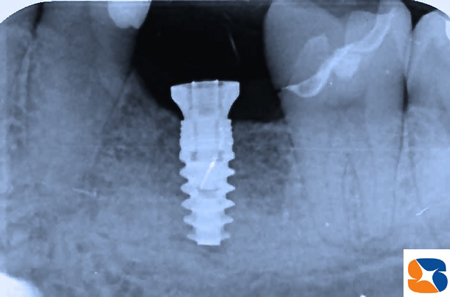

ところが、欠損部の横の歯が、かなり後ろに傾いています。このようなケースでは、植立したインプラントの角度や深度にミスが生じやすくなります。そこで、ノーベルバイオケア社製の「サージカルガイド」を使用して確実な手術を行う計画をたてました。

ノーベルクリニシャンを使って、インプラントの適正な植立位置(角度、深さ)や仮想の歯をシュミレーションします。このデーターをノーベルガイド社に送信して、ガイドを注文しました。

出来上がったサージカルガイドを使って手術が始まりました。

ガイドを使用すれば、神経を傷つけたり、アゴを突き抜くような事故がなくなるので、患者様も安心して手術を受けて頂けます。

サージカルガイドどは、ドリル器具がわずか1㍉、わずか1°の角度もズレることなく安心・安全に手術を進めるための医療器具です(当院では追加料金なし)。

※ 使用インプラントメーカー:ノーベルバイオケア社製のアクティブ直径4.3-長さ11.5㍉